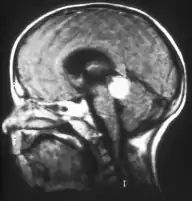

Aspect of trilateral retinoblastoma on MRI

Inherited forms of retinoblastomas are more likely to be bilateral. In addition, inherited uni- or bilateral retinoblastomas may be associated with pineoblastoma and other malignant midline supratentorial primitive neuroectodermal tumors (PNETs) with a dismal outcome; retinoblastoma concurrent with a PNET is known as trilateral retinoblastoma.[15] A 2014 meta-analysis showed that 5-year survival of trilateral retinoblastoma increased from 6% before 1995 to 57% by 2014, attributed to early detection and improved chemotherapy.[16]